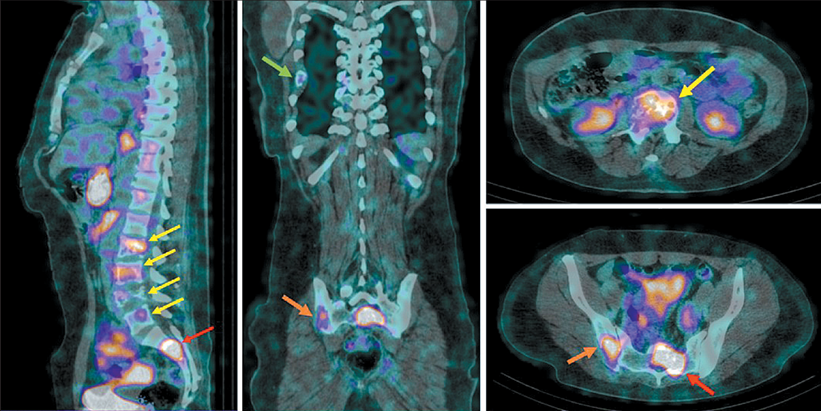

Клинический случай № 2. Пациентка Д., 42 года, диагноз: Рак правой молочной железы IV стадии (T1N1M1), метастаз в аксиллярный лимфоузел, множественные метастазы в костях. ОФЭКТ/КТ проведена через 2 ч после инъекции РФЛП [99mTc]Tc-DB8 в дозировке 80 мкг, при которой помимо визуализации первичного очага и метастатически измененного лимфоузла выявлена высокая аккумуляция РФЛП в проекции LII-SII, в подвздошной и седалищной костях, в заднем отрезке VII ребра справа.

4. Рис. 4. ОФЭКТ/КТ больной Д. через 2 ч после инъекции [99mTc]Tc-DB8 в дозировке протеина 80 мкг. Стрелками отмечены участки гиперфиксации РФЛП в проекции тел LII-LV (желтая стрелка), S1-SII (красная стрелка), подвздошной и седалищной костей справа (оранжевая стрелка), заднего отрезка VII ребра справа (зеленая стрелка). Примечание: рисунок выполнен авторами